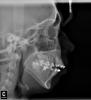

Trash Опубликовано 11 июля, 2011 Поделиться Опубликовано 11 июля, 2011 Здравствуйте! Ношу брекеты 8 месяцев. У меня открытый прикус, сужение верхней челюсти, челюсть выдается вперед (видно на снимке ниже). Перед установкой Daimon Q мне удалили все 4-ки. Щели почти затянулись, но проблема выпирающей челюсти не была решена. Никаких приспособлений для расширения челюсти мне врач не ставил. Теперь предлагают удалить еще две 8-ки на верней челюсти (чтобы задвинуть челюсть назад), поставить два микроимпланта в области 7-ок (чтобы приподнять челюсть для нормализации прикуса). Возможно, что по окончании лечения придется удалить еще и две 8-ки на нижней челюсти (не знаю зачем, не объяснили). Я спрашивала у врача насчет установки какого-нибудь небного расширителя, так как у меня узкое лицо и мне хотелось бы немного исправить эту проблему. Но врач сказал, что в моем возрасте (мне 22 года) этим уже не поможешь и добавил, что научит делать упражнения для расширения челюсти (надо делать движения языком по небу, как будто разминаешь жвачку). Для меня непонятно, почему небный расширитель в моем случае неэффективен, а обычные упражнения принесут желаемый результат? И меня также беспокоит такое количество удаляемых зубов. Я читала, что после удаления 8-к щеки могут "запасть" и лицо еще больше вытянется - этот вариант явно не для меня. Хотелось бы услышать альтернативные метода решения моей проблемы. Может быть кто-нибудь сталкивался с такой проблемой? Ссылка на комментарий